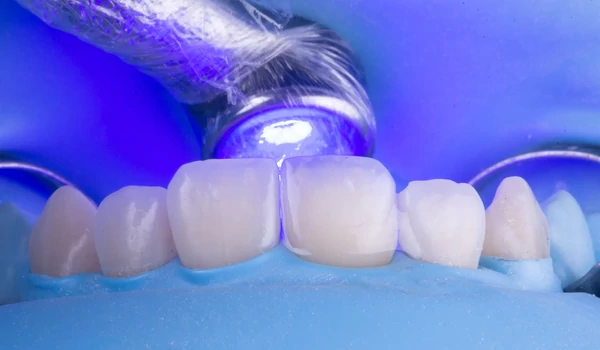

A klinikai beavatkozás lépései1. Izoláció és a régi restauráció eltávolításaA fogat kofferdámmal izolálták, majd eltávolították a rosszul illeszkedő régi kompozit restaurációt. Megállapították, hogy a gyökértömés túl koronálisan volt levágva, ami elszíneződés kockázatát rejti magában. Ezért a gutta-perchát a megfelelő biológiai szintre visszaszivattyúzták egy downpack eszköz segítségével kuraraynoritake.eu. |

2. ábra. A munkaterület izolálása kofferdámmal: frontális nézet. |

3. ábra. A munkaterület izolálása kofferdámmal: okkluzális (rágófelszíni) nézet. |